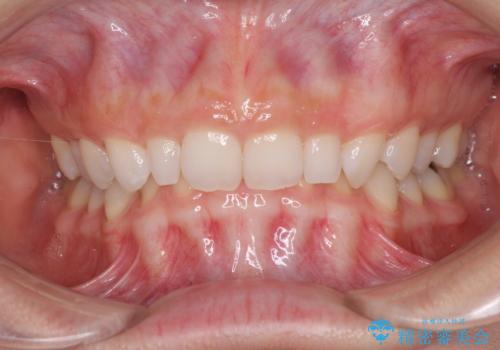

受け口と八重歯を改善 インビザライン矯正治療